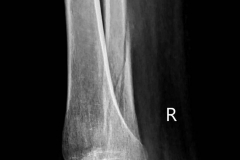

3 months past... My leg still broken , but today my doctor say: I see good changes!!! Unfortunately I can't make complicated things while leg is broken.But I will try. #x-ray